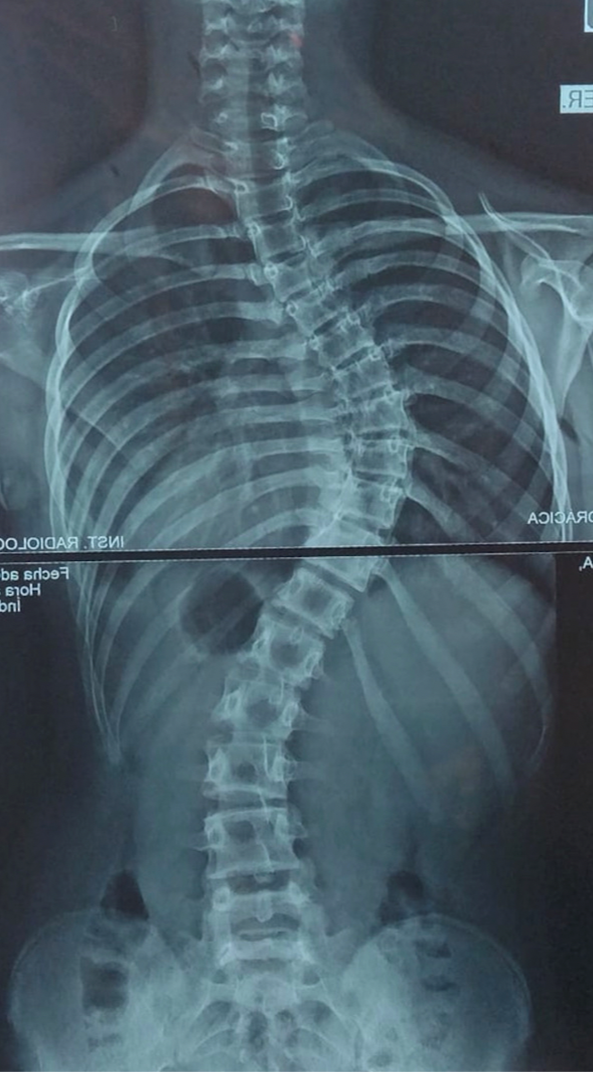

A principio del 2021 comenzamos las consultas con Dr. Pablo Fiorillo, tras unos meses de seguimiento y viendo que la curvatura seguía avanzando (+de 60⁰) decidió que la mejor opción era la cirugía.

La operación se llevó a cabo el martes 7 de junio 2021 en el Sanatorio de Niños de Rosario, duró 6 horas y constó de la colocación de una barra de fijación de cobalto y 22 tornillos. El sábado 11 de junio ya recibíamos el alta. A las tres semanas volvió a la escuela, al mes andaba en bicicleta y a los 4 meses ya hacía vida normal nuevamente e hizo su viaje de séptimo realizando todas las actividades sin preocupaciones. Destacamos el profesionalismo, la calidad humana y el excelente trato del Dr. Pablo Fiorillo para con sus pacientes. Nos brindó mucha ayuda, nos transmitió la tranquilidad, siempre presente antes y después de la operación. No tenemos dudas que nuestra hija estuvo en las mejores manos.